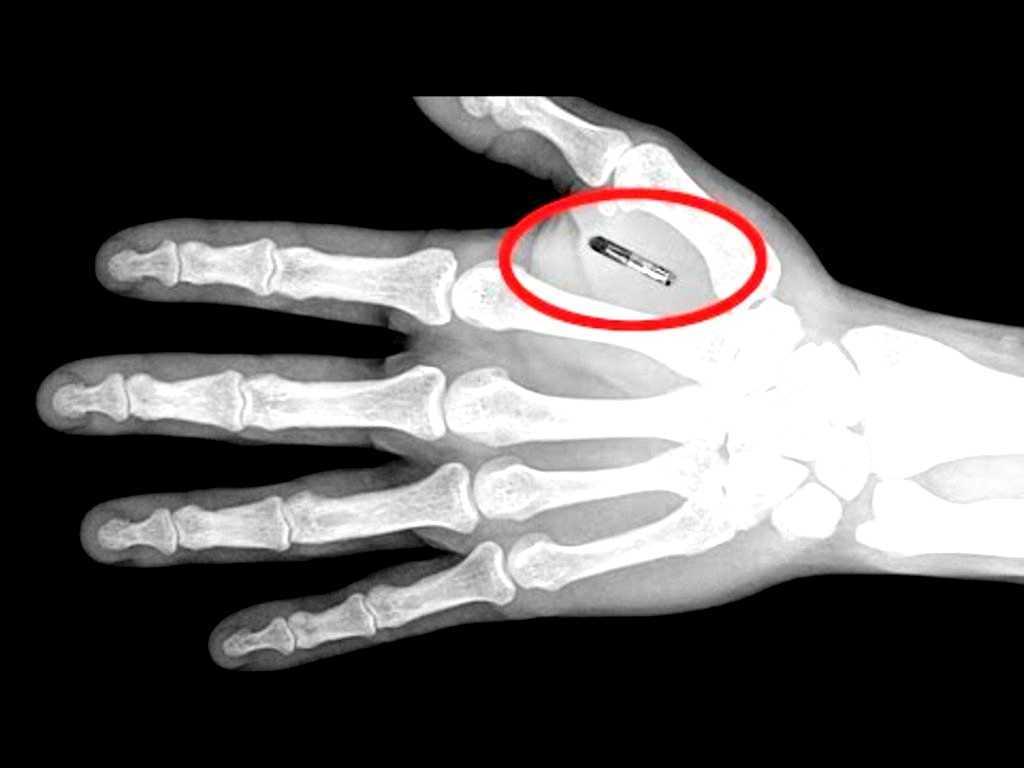

A human microchip implant is typically an identifying integrated circuit device or RFID transponder encased in silicate glass and implanted in the body of a human being. This type of subdermal implant usually contains a unique ID number that can be linked to information contained in an external database, such as personal identification, law enforcement, medical history, medications, allergies, and contact information.

About the size of a grain of rice, the device was typically implanted between the shoulder and elbow area of an individual's right arm. Once scanned at the proper frequency, the chip responded with a unique 16-digit number which could be then linked with information about the user held on a database for identity verification, medical records access and other uses. The insertion procedure was performed under local anesthetic in a physician's office.